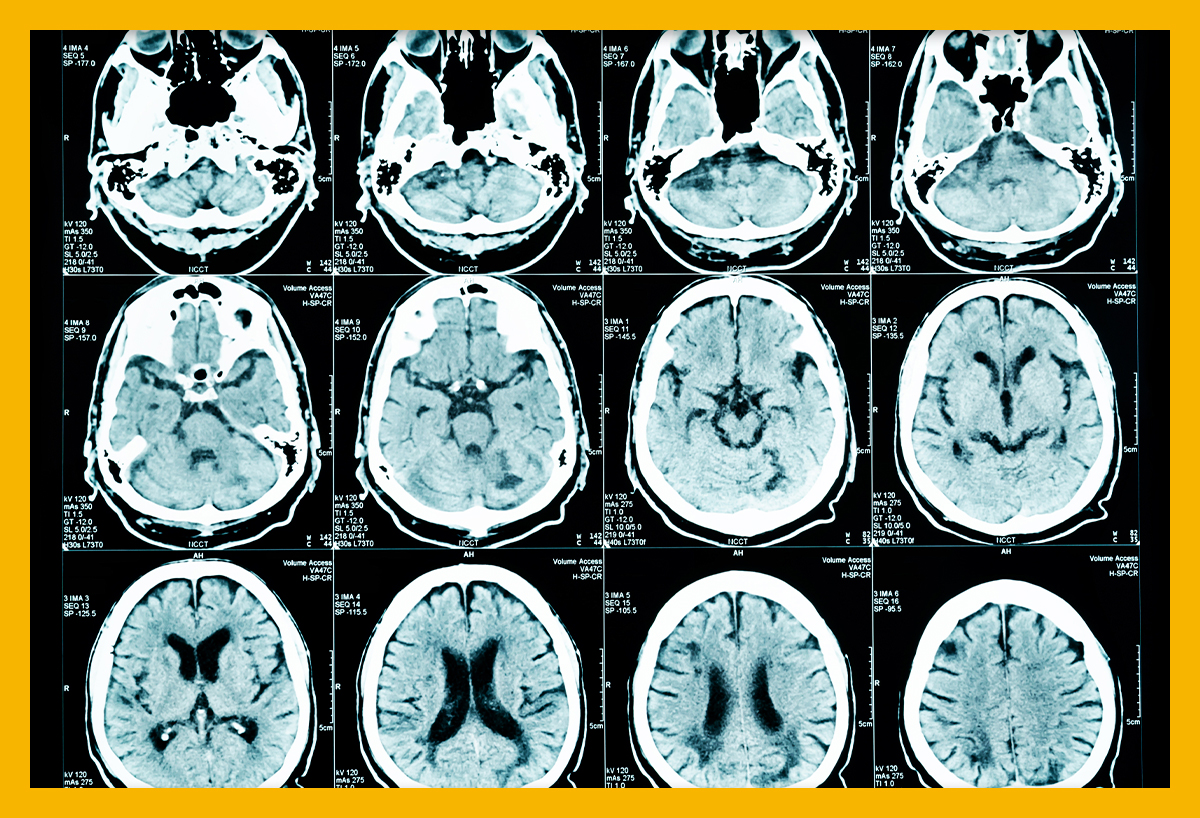

다른 뇌질환들과 달리 주변 시야가 좁아져요. 물체가 여러 개로 겹쳐 보이는 증상들이 아무런 징후도 없이 급격하게 유발돼요. 혈관이 막히면 바로 뇌 손상을 입는 환자가 있답니다. 혈관이 막혔더라도 다른 혈관으로 혈액 순환이 일정 시간 할 수 있는 환자도 있어요. 또한 혈관이 일시적으로 막혔다가 다시 뚫리면서 증세가 완화되거나 없어지는 경우도 있어요.통상 뇌경색 환자 5명 중 1명 꼴로 나타나는 증상입니다. 시력저하는 나이가 들며서 자연스럽게 나타나는 현상이라고 생각하고 쉽게지나치는 경향이 있어요. 시력 저하가 갑자기 발생하면 뇌경색을 의심할 수 있으니, 병원에 방문하시길 권해드리도록 하겠습니다.